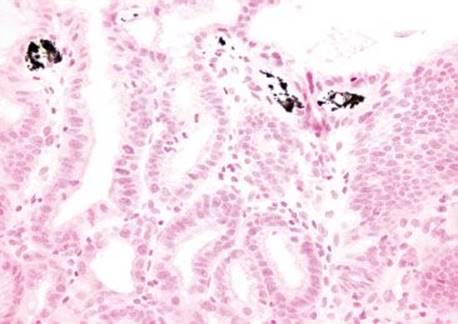

Figure 2.228 Iron pattern B/“iron pill gastritis”. Pigment in the stomach can herald a variety of etiologies and consumables. In this example, the golden pigment of iron is seen embedded in the superficial mucosa and within the luminal debris. This case was submitted as “rule-out carcinoma” based on the ominous endoscopic impression.

Gastric iron deposition is seen in up to 3.8% of upper tract biopsies (Fig. 2.228).23,24,183–185 In a study of 500 gastric biopsies, the deposition was demonstrated in three generalized patterns. Pattern A (also referred to as “nonspecific gastric siderosis”) was the most common subpattern and involved 2.2% of specimens (Figs. 2.229 and 2.230). This subpattern was associated with prior mucosal microhemorrhages, and the subtle depositions were predominantly identified within macrophages and stromal cells of the lamina propria. Pattern B (also referred to as “iron pill gastritis”) was seen in 0.8% of the biopsies and was consistently associated with ferrous sulfate therapy. This deposition was coarse and crystalline and predominantly identified in the extracellular and most superficial aspect of the biopsy (Figs. 2.231–2.234). In this subpattern, the background mucosa had a reactive gastritis/gastropathy pattern with erosions, ulcerations, and fibrino-inflammatory exudate common. In a separate study of 1,300 gastric biopsies, a similar “iron pill gastritis” injury pattern was detailed.184 This latter group reproduced the identical iron deposits in the laboratory by oxidizing ferrous sulfate tablets, providing clear evidence for the iron origin of these deposits. The mechanism of injury is a bit unclear in this subpattern. Some speculate that the iron pill has a direct caustic effect on the adjacent mucosa, whereas others suggest that the iron deposits may simply colonize previously injured mucosa. Pattern C (also referred to as “gastric glandular siderosis”) was the least common pattern, involving 0.6% of the specimens. This subpattern was associated with iron overload settings, such as hereditary hemochromatosis and multiple blood transfusions. The characteristic deposits were subtle, uniform, and identified in the deep antral and oxyntic glands (Figs. 2.235–2.239). The iron deposits can be highlighted blue with a Prussian blue iron special stain. Recognition is important to help prevent further injury and potential stricture formation (pattern B), to suggest pertinent iron overload evaluation (pattern C), and to avoid overdiagnosing the marked reactive epithelial change as dysplasia.

Anecdotally, iron pill gastritis is not an uncommon specimen rushed for a clinical concern for carcinoma. The endoscopic and histologic features can appear equally ominous, making it easy to misdiagnosis malignancy if the associated iron pill injury pattern is not recognized. In general, before diagnosing malignancy, always scrutinize the tissue and surrounding luminal debris for any benign excuse that might account for the horrendous atypia. When in doubt, a Prussian blue iron special stain can be reassuring.